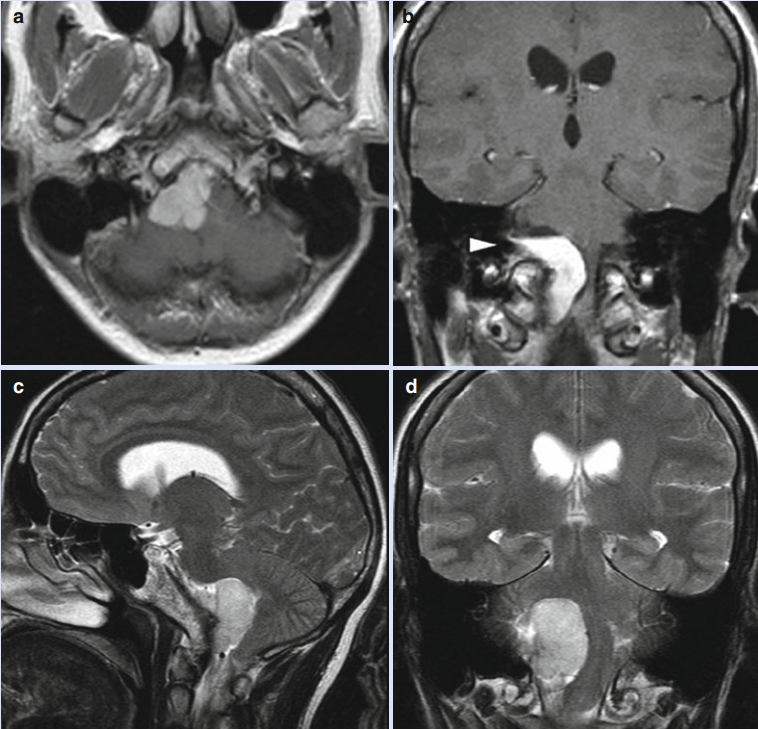

42歲的女士 Amanda1年前頸部右側(cè)劇烈疼痛,同時(shí)伴有頭痛和眩暈癥狀,去醫(yī)院就診MRI研究顯示,在橋小腦角區(qū)有一個(gè)相對(duì)較大的腫瘤,并向尾側(cè)延伸至枕骨大孔水平(a–d),累及頸靜脈孔(b箭頭),該腫瘤導(dǎo)致腦干嚴(yán)重受壓和移位??紤]到腫瘤位于大腦“橋小腦角區(qū)”——此區(qū)域曾被稱為“血腥三角”,匯集了眾多血管和重要功能神經(jīng),既要把腫瘤切除干凈,確定后期不復(fù)發(fā),又要降低對(duì)正常神經(jīng)功能的損傷,這對(duì)于醫(yī)生的手術(shù)技術(shù)、醫(yī)療團(tuán)隊(duì)的配合程度和醫(yī)院的術(shù)中輔助設(shè)備要求都很高。 Amanda經(jīng)過多方查詢了解,較后找到國際顱底腫瘤手術(shù)教授INC德國巴特朗菲教授進(jìn)行診斷和治療。

MRI術(shù)前檢查在橋小腦角區(qū)有一個(gè)相對(duì)較大的腫瘤,并向尾側(cè)延伸至枕骨大孔水平(a–d),累及頸靜脈孔(b箭頭)

巴教授根據(jù)患者的術(shù)前病灶判斷此腫瘤為枕大孔區(qū)腦膜瘤,根據(jù)腫瘤具體位置和形態(tài)制定了個(gè)體化的手術(shù)方案。